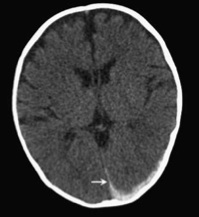

During nine days of testimony over three weeks, the jurors heard from nine medical experts for the prosecution, including the local medical examiner, a child-protection pediatrician, a pediatric ophthalmologist, a pediatric radiologist, two pediatric critical-care physicians, and a specialist in osteogenesis imperfecta (OI), a disease of the bones. All agreed that Annie had died from abusive head trauma. Many said shaking was involved.

Ashley cautioned against drawing any lessons or conclusions from this “nuanced” case, which he said was not about shaken baby syndrome. “The prosecution threw shaken baby syndrome at this couple,” he said, “Our case was about accidental, non-intentional head trauma exacerbated by OI.”